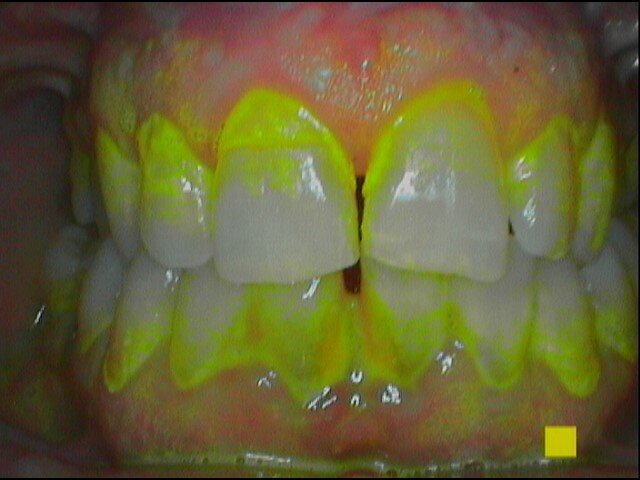

Vengono rilevati gli indici clinici e vengono condivise con il paziente le immagini raccolte con la videocamera intraorale, così da motivarlo di fronte alla presenza di tartaro e infiammazione gengivale e mostrargli le aree critiche. Viene apposto il rilevatore di placca alla fluorescina ed illuminato da una lampada fotopolimeralizzante, che permette di visualizzare la topografia del biofilm batterico (D-BIOTEK-TECNICHE)2, in modo da condividere con il paziente i siti più a rischio del cavo orale (Figg. 1a-2f).